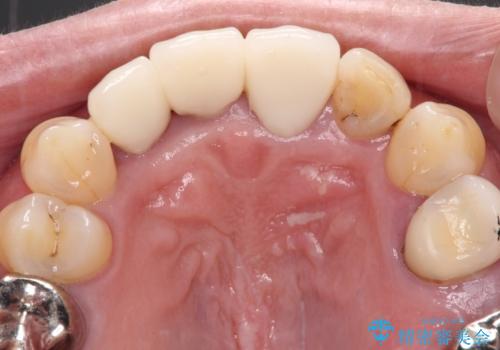

歯肉の位置は変更できないため、露出している歯根をクラウンで覆い隠すと歯が長く見えることを事前にお伝えしておりました。

真ん中2本は治療前よりも短めに仕上げることで、極端に長い印象を避けることができました。